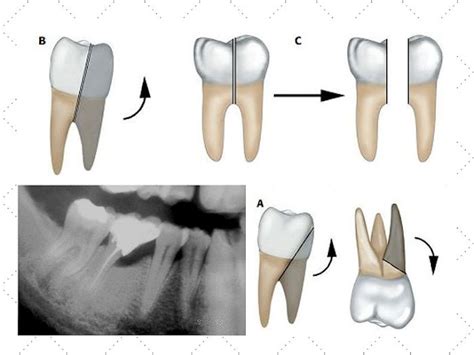

Una de las posibilidades terapéuticas es la resección radicular (RR), definida como la remoción quirúrgica de una o más raíces de un diente multirradicular, incluyendo o no su área coronal correspondiente. Este procedimiento permite mantener dientes que estaban destinados a la exodoncia y debe ser seguido por una restauración que preserve las condiciones periodontales y los principios restauradores.

En la restauración de molares con RR, se deben considerar factores relacionados con las características anatómicas específicas resultantes del procedimiento. Debido a que las raíces de los molares son más estrechas mesiodistalmente y más amplias bucolingualmente que los dientes unirradiculares, se requieren modificaciones en el diseño de la preparación protésica. Es fundamental un perfil de emergencia plano del margen de la preparación para facilitar el control de la placa bacteriana.

El tipo de margen de la corona completa también es importante. Debido a la limitada amplitud residual, se recomiendan terminaciones en filo de cuchillo para evitar la remoción excesiva de estructura dentaria. En el área cervical, esta línea de terminación es trascendental para lograr un efecto férula. Finalmente, para disminuir las cargas oclusales excesivas, es fundamental reducir las inclinaciones cuspídeas de la restauración.

Asumiendo una distancia de 2 mm para la amplitud biológica y 1,5 mm para la estructura dentaria requerida para lograr un efecto férula en la corona, se requiere un mínimo de 3,5 mm disponibles entre la cámara pulpar y el margen coronal de las raíces residuales. Sin embargo, estudios han demostrado que en muchos casos, la estructura dentaria disponible es menor a 3 mm, lo que implica que las restauraciones se extienden subgingivalmente.

Un aspecto fundamental en los procedimientos de RR es el contorneado óseo para recrear una arquitectura positiva, donde los colgajos deben ser posicionados apicalmente para facilitar la higiene bucal. La presencia de remanentes de las raíces (labios radiculares) no detectados durante la cirugía debe ser eliminada durante la fase restauradora para prevenir la acumulación de placa y la progresión de la enfermedad periodontal.